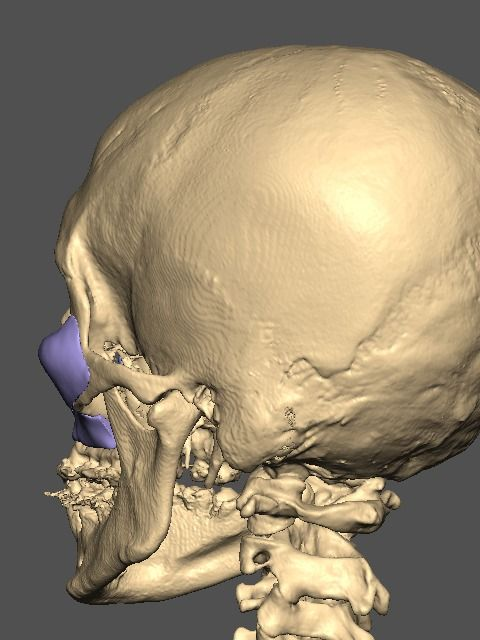

A lot changed since the initial design

It's going to be split into either 5 or 7 pieces.